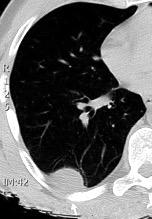

Absceso pulmonar por Neiseria y Est. Viridans. “Borde mal definido”.

Cavidad en el centro de la densidad

Empiema pleural en adicto. “Borde bien definido”.

Cavidad en el ápice

DD et al . Differentiating abscess and empiema: Radiography and computed tomography. AJR.1983